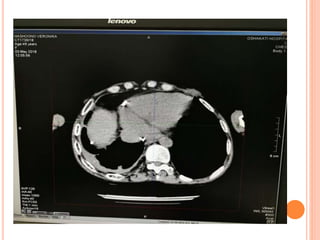

CT scans

Lung Window